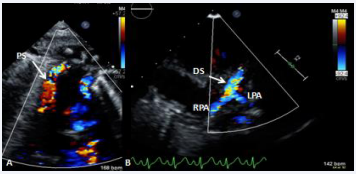

Figure 25 Selected video frames from suprasternal notch view demonstrating bidirectional Glenn shunt; the superior vena cava (SVC) is shown emptying into the right (RPA) and left (LPA) pulmonary arteries by color flow imaging (A). Low Doppler flow velocity across the shunt (B) indicates unobstructed Glenn [69].

Figure 25 :Selected video frames from suprasternal notch view demonstrating bidirectional Glenn shunt; the superior vena cava (SVC) is shown emptying into the right (RPA) and left (LPA) pulmonary arteries by color flow imaging (A). Low Doppler flow velocity across the shunt (B) indicates unobstructed Glenn [69].

Figure 26 Selected video frames from suprasternal notch view demonstrating bidirectional Glenn shunt; the superior vena cava (SVC) is shown emptying into the right (RPA) and left (LPA) pulmonary arteries by two dimensional (A) and color flow imaging (B) [69].

Figure 26: Selected video frames from suprasternal notch view demonstrating bidirectional Glenn shunt; the superior vena cava (SVC) is shown emptying into the right (RPA) and left (LPA) pulmonary arteries by two dimensional (A) and color flow imaging (B) [69].

Echocardiographic and angiographic examples of the bidirectional Glenn procedure are shown in Figures 25-28.